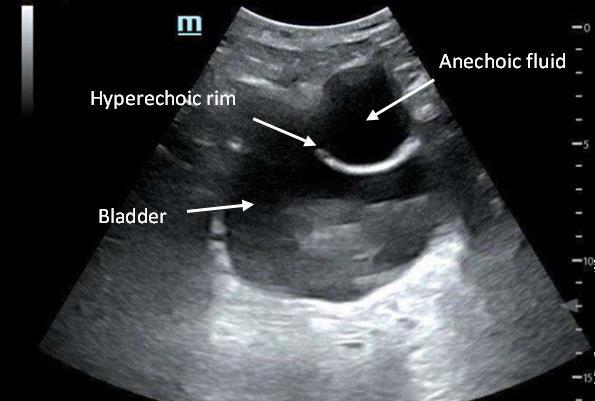

Prior to the start of the procedure, the patient must have IV access and be placed on a cardiac monitor. After informed consent has been obtained, the patient is positioned in the supine position with the head to the contralateral side of the proposed block. The physician stands at the head of the bed above the ipsilateral breast with the ultrasound screen in direct line of sight (commonly at the level of the contralateral hip). The ultrasound probe is initially placed in the sagittal plane at the midclavicular line until the clavicle, pectoralis muscles, and axillary artery and vein are visualized. The transducer is then translated caudally until the third and fourth intercostal spaces are visualized (Image 1).

At this point, the pectoralis major and minor muscles can be visualized. By rotating the transducer 45 degrees clockwise, the thoracoacromial artery can be identified between the pectoralis major and minor muscles. Also, the serratus anterior muscle should be identified resting just above the anechoic rib (Image 2).

Image 1. Initial probe placement for the pectoralis nerve block I and II illustrated on a model: the blue line indicates transducer, and the green dot indicates directional marker corresponding to ultrasound image. Image 2. Final probe placement prior to the pectoralis nerve block I and II: blue line indicates transducer, and green dot indicates directional marker corresponding to ultrasound image.